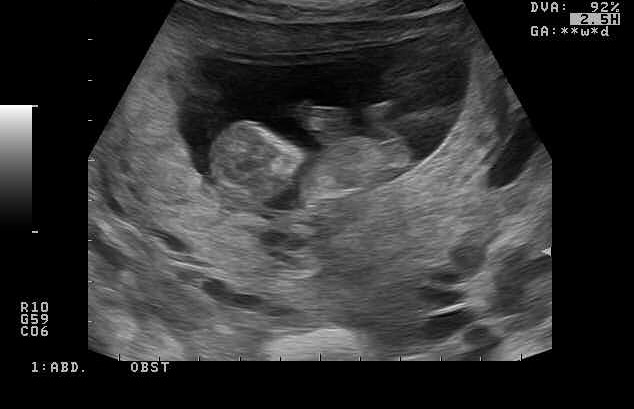

Hi everyone,

I just got my 13.3 week scan Hope to hear some guesses

Are these photos of a screen? do you happen to have a video you could post for us:) I am unable to zoom your current pictures at all so cannot make any guess atm.

No I don't have a video. When I zoom the pic in I can't upload them anymore. I will try it again